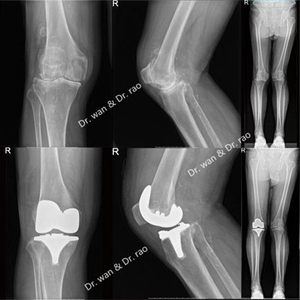

王先生今年84岁,双侧膝关节疼痛难忍10余年。其妻子十年前曾在外院做过膝关节置换手术,由于术后效果并不理想,导致王先生对关节置换手术顾虑重重,甚至对关节置换手术产生心理恐惧。近年来,王先生自觉双侧膝关节疼痛加重,无法下蹲,上下楼梯困难,平地行走疼痛加剧,休息后疼痛无法完全缓解,诊断为骨关节炎膝外翻畸形。虽然王先生有明确的关节置换手术指征,但由于他对关节置换的恐惧心理,只于一年前在外院行膝关节镜手术治疗,术后关节疼痛无法缓解,严重影响日常生活。

近日,王先生终于被女儿说服,在女儿的陪同下,慕名来到同济大学附属同济医院骨科就诊并住院治疗。在骨科关节外科副主任饶志涛的带领下,经过副主任医师万大千周密的检查和关节外科全科病例分析,根据骨科学科带头人程黎明教授《运动骨关节病学》中对骨性膝关节炎的分型介绍,确诊该患者已出现膝关节畸形——膝外翻情况。因此,骨科团队为患者量身定制了手术方案,决定为其进行全膝关节置换术治疗。手术非常顺利,下肢力线和软组织平衡完美恢复,患者术后第一日疼痛明显缓解,即刻下地行走。王先生对关节置换手术疗效和快速康复非常满意,恐惧心里也因此烟消云散。